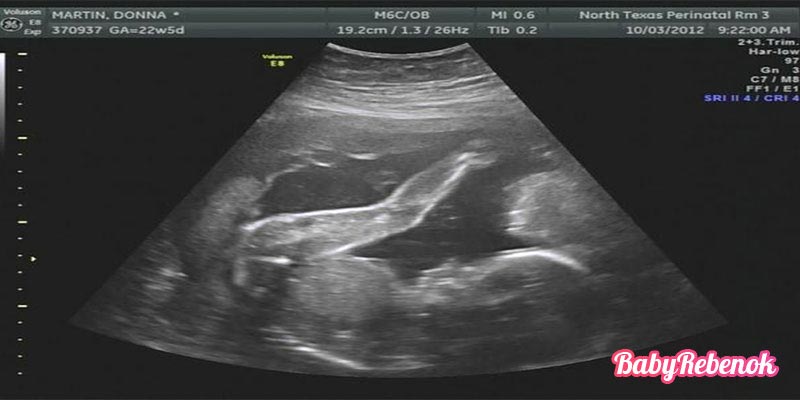

УЗИ на 22 неделе беременности

Ультразвуковое исследование назначается в том случае, если до сих пор не пройдено второе обязательное УЗИ.

Биометрические параметры плода, которые исследует специалист:

- Длина от темени до копчика

- Длина бедра

- Длина руки

- Размер головы

На основании результатов УЗИ делается вывод о соответствии эмбриона сроку беременности.

Кроме того, врач оценит количество и качество амниотической жидкости и толщину и зрелось плаценты. На этом сроке защитная оболочка плода должна иметь нулевую зрелость и примерно 22 мм толщины.

УЗИ на 22 неделе

Второе по плану УЗИ делают на 22 неделе беременности. В процессе этого УЗИ ваш врач проверит нет ли у ребенка допустимых пороков, исследует степень развития внутренних органов.

На данной неделе беременности копчиково-теменной размер уже не играет такую роль в плане установление нормы в развитие плода. В противоположность этому, врач смотрит на общее соотношение пропорций тела.

Вместе с этим, специалист анализирует число и прозрачность амниотической жидкости, после этого устанавливает уровень много- или маловодия, обследуют состояние пуповины и плаценты.

На 22 неделе все еще возможно произвести второе скрининговое УЗИ, если не успели на 21-й. Хорошо видны все органы плода и специалист внимательно оценивает их форму, размеры, исключает наличие пороков.

Кроме того, в протокол исследования включены обязательная оценка соответствия размеров плода сроку беременности, размеры, расположение, состояние плаценты.

Обязательными являются следующие измерения: бипариетальный размер, окружность головки, окружность живота, бедренная кость, плечевая кость, кости предплечья, кости голени и их оценка с помощью таблиц.

УЗИ на 22 неделе беременности является обязательным, плановым скринингом. Здесь врач исследуя плод выявляет возможные пороки развития. Оценивает развитие внутренних органов ребенка на данном этапе, а также устанавливает параметры развития тела малыша. Определяет уровень околоплодных вод, состояние пуповины и плаценты.